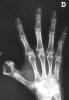

Carpo normal

ACT Alteraciones degenerativas en muñeca.